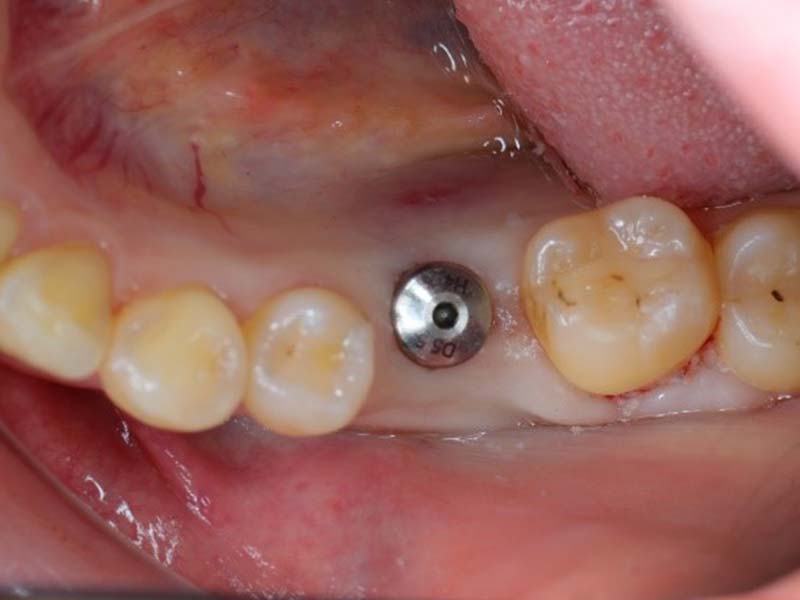

利用CT影像及口掃檔清楚掌握患者口腔內骨頭、牙齒、神經與血管的位置,事前模擬植體位置,並利用 3D 列印做出手術導板,確保植入深度與位置都恰如其分,在手術中能控制植體精準的位置與深度,避免傷及神經血管、打穿鼻竇,又足以讓齒槽骨牢牢地抓住人工牙根。

電腦輔助設計,完整考量咬合及負重分散,並以手術導板輔助精準地植入植體,延長植體的使用壽命。

植牙的成功與否不只要靠醫師的技術,還要加上術前仔細評估、手術過程精準、術後照護等因素,才能保證植牙治療的品質。 根據醫學研究報告顯示,一旦植體放入的位置不當,不僅會造成往後的假牙製作不易,更容易出現斷裂或發炎等問題,導致植牙失敗。在植牙過程中,病患不自主的小動作(如吞嚥口水、嘔吐反射、嘴巴張不開等),也都會影響植體放入的角度,只要位置不夠精準,植牙治療效果就會大打折扣。植牙手術導板可製化,針對不同病患設計,提高植牙成功率。建議民眾在接受植牙治療時,可藉由植牙手術導板精準定位,達到成功植牙的治療成果。